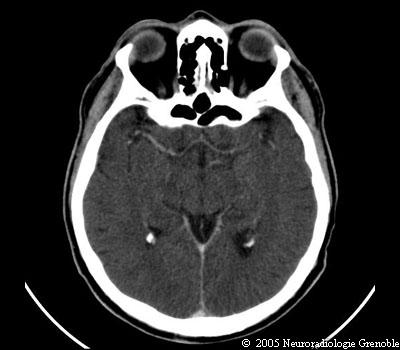

Radioanatomie TDM de l'encéphale

TDM cérébrale sans injection